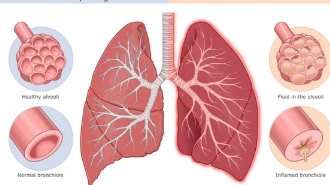

1. 기침과 호흡 곤란

방사선 폐렴은 초기 단계에서 잦은 기침과 숨 가쁨을 동반하는 경우가 많습니다.

- 마른 기침:

처음에는 마른 기침으로 시작되며, 감기와 비슷한 양상을 보입니다. 시간이 지나면서 기침이 점점 심해질 수 있습니다. - 호흡 곤란:

평소에는 문제없이 걸어 다녔던 환자가 갑자기 계단 오르기가 어려워지고, 가벼운 활동에도 숨이 찬다고 느끼는 경우, 방사선 폐렴 초기 증상일 가능성이 있습니다. - 천명음:

숨을 들이쉴 때 쌕쌕거리는 소리나 가슴 속에서 휘파람 소리가 들릴 수도 있습니다.

방사선 폐렴이 치료 없이 방치되면 폐 기능이 점점 악화될 가능성이 높습니다.

- 폐활량 감소:

폐가 딱딱해지는 섬유화 현상이 진행되면서 숨을 깊이 들이쉬기가 어려워지고, 폐활량이 감소합니다. - 산소 부족 증상:

피부가 푸르스름해지는 청색증이 나타나거나, 운동 중 어지러움이나 혼란 상태가 발생할 수 있습니다. - 만성 폐질환으로 진행 가능성:

초기 단계에서 치료하지 않으면 만성 폐섬유증으로 발전해 장기적인 호흡 문제가 생길 수 있습니다.